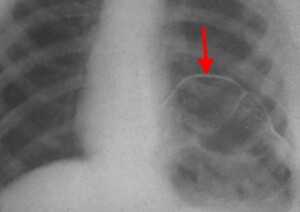

Нейрогенные парезы дыхательной мускулатуры осложняют течение ряда заболеваний центральной и периферической нервной системы. В отдельных случаях они могут быть преобладающими или единственно манифестными, вызывая диагностические трудности имитацией заболеваний дыхательной системы. Парезы диафрагмы и развившаяся на этом фоне дыхательная недостаточность могут быть следствием множества патологических процессов, включая миелит, болезни мотонейрона, полинейропатии, болезни нервно-мышечных синапсов, некоторые миопатии, герпетические полирадикулоневриты, травматические повреждения диафрагмального нерва, поражения шейного сплетения, заболевания грудной клетки и поддиафрагмальные патологические процессы [17]. Причины дисфункции диафрагмы можно классифицировать в зависимости от уровня поражения [4]. Продолговатый или спинной мозг поражается при демиелинизирующем процессе, однако парез диафрагмы довольно редко встречается при рассеянном склерозе [12, 18]. Высокое поражение спинного мозга (на уровне С1 или С2) приводит к параличу диафрагмы, в то время как при среднешейном поражении (на уровне С3-С5) функция диафрагмы частично сохраняется. Около 40% пациентов с поражением на уровне С3 нуждаются в искусственной вентиляции легких (ИВЛ), и лишь 15% пациентов с повреждением на уровне С4 или С5 [18, 33]. Заболевания верхних мотонейронов спинного мозга, как, например, боковой амиотрофический склероз или полиомиелит, часто приводят к дисфункции диафрагмы и дыхательной недостаточности. Парез диафрагмы может развиться как непосредственно сразу после инфицирования вирусом полиомиелита, так и спустя многие годы (в среднем, 35 лет) [9, 18]. К другим причинам, вызывающим парез диафрагмы и захватывающим мотонейроны спинного мозга относятся сирингомиелия, паранео-пластические моторные нейропатии и спиналь-ные мышечные атрофии. В большинстве случаев причиной осложнений и летального исхода при этих состояниях является дыхательная недостаточность [18]. Повреждение непосредственно самого диафрагмального нерва - чаще всего результат ятрогенного воздействия на него во время операции или сдавления опухолью [18, 21, 28]. В литературе описаны случаи проявления аневризмы грудного отдела аорты в форме паралича диафрагмального нерва. Симптомы также включали дисфонию, хроническую боль в груди и прогрессирующую дисфагию [5, 24]. К другим состояниям, способным вызвать непосредственное поражение диафрагмального нерва можно отнести травмы, инфекционные поражения (герпетическая инфекция, болезнь Лайма) и воспалительные процессы. Синдром Гийена-Барре часто осложняется вовлечением диафрагмального нерва [18, 31]. Так, от 20% до 30% госпитализированных пациентов с установленным диагнозом синдрома Гийена-Барре нуждаются в эндотрахеальной искусственной вентиляции легких [15]. Согласно данным исследования в Англии 25% и 23% [15] больным синдромом Гийена-Барре необходима ИВЛ [6]. Известно, что приблизительно у 5% пациентов с невралгической амиотрофией (синдромом Пэрсонейдж-Тёрнера) имеется вовлечение диафрагмального нерва [18, 29]. Болезни с нарушением синаптической передачи могут манифестировать с дисфункции диафрагмы. Острая дыхательная недостаточность часто возникает при миастеническом кризе, что приводит к необходимости искусственной вентиляции легких. Реже дисфункция диафрагмы встречается при синдроме Ламберта-Итона, ботулизме, наследственных и приобретенных миопатиях, а также при отравлении аминогликозидами, фосфорорганическими веществами [18]. Важно помнить о вероятности развития атрофии диафрагмы, которая может возникнуть даже после короткого периода искусственной вентиляции легких. Она связана с атрофией как быстро, так и медленно сокращающихся мышечных волокон. Так, недостаточное питание или такие метаболические сдвиги, как гипофосфатемия, гипомагниемия, гипокалиемия, гипокальциемия могут способствовать дисфункции диафрагмы и продлевать потребность в искусственной вентиляции [14, 18, 19]. Среди пациентов с диспноэ, ортопноэ или гиперкапнической дыхательной недостаточностью неуточненной этиологии следует учитывать возможность наличия нейропатии диафрагмального нерва (НДН) [30]. В современной литературе она часто описывается в сочетании с болью в шее и плече, часто возникающей после инфекционных заболеваний или операций, что позволило считать НДН возможной состовляющей невралгической амиотрофии плечевого пояса (синдрома Персонейджа-Тернера). Идиопатическая НДН, вероятно, является отдельной нозологической формой в спектре иммуноопосредованных фокальных нейропатий, и, напротив, не ассоциирована с такими симптомами как боли в плече, шее, парезом верхней конечности [16, 17, 20, 23, 29, 30, 32]. Различают одностороннюю и двустороннюю НДН. Односторонняя НДН зачастую не приводит к значимым дыхательным нарушениям и протекает клинически бессимптомно, что объясняет ее гиподиагностику и, как следствие, малую распространенность описаний в литературе [16, 23]. Интерес представляет клиническое наблюдение НДН, сделанное в нашей клинике. Больной К., 39 лет, поступил в приемное отделение Республиканской клинической больницы 09.04.2015 г. с жалобами на выраженную одышку экспираторного характера в покое, сухой непродуктивный кашель, повышение температуры до 37,6˚С. Заболел около 3 недель назад, когда на фоне полного здоровья появилась одышка в покое, усиливающаяся при физической нагрузке, надевании специализированной формы (больной работает пожарным). Одышка продолжалась на протяжении около 2 недель, затем присоединилось повышение температуры до 37,5˚С, кашель. Отмечает, что за неделю до начала заболевания появились ноющие боли в плече, не связанные с движением, продолжались 2 дня, затем появились ноющие боли в шее, которые купировались внутримышечным введением диклофенака в течение 3 дней. У пациента из сопутствующих заболеваний в анамнезе вирусный гепатит С, минимальной степени активности, по поводу чего один год назад получал лечение интерфероном. Пациент не злоупотребляет алкоголем, курил с 16-летнего возраста в течение 23 лет по 1-2 пачки сигарет в день, бросил курить в ноябре 2014 года. Наследственный анамнез не отягощен. При поступлении общее состояние тяжелое ввиду диспноэ. Температура тела 37,6˚С. Телосложение правильное, питание достаточное, костно-мышечная система без особенностей. Кожа и видимые слизистые физиологической окраски, теплые, нормальной влажности. Дыхание жестковатое, ослаблено в нижних отделах, хрипов нет, ЧДД 19 в минуту. Сатурация кислорода 93% без подачи кислорода. Тоны сердца приглушены, ритмичные, АД 160/100 мм рт. ст., ЧСС 89 в минуту. Живот мягкий, безболезненный, на вдохе западение передней брюшной стенки. Периферических отеков нет. В неврологичес- ком статусе: сознание ясное, поведение адекватное, команды выполняет. ЧМН: без особенностей. Объем активных и пассивных движений конечностей полный. Мышечная сила достаточная по всем группам. Сухожильные рефлексы с верхних и нижних конечностей равные, живые. Поверхностная, глубокая чувствительность не изменена. Координаторные пробы выполняет удовлетворительно, в пробе Ромберга устойчив. Менингеальных знаков нет. Функции органов таза не нарушены. Пациент был переведен в отделение реанимации и интенсивной терапии и подключен к аппарату “Dager Savina” в режиме BIPAP для проведения неинвазивной масочной ИВЛ. Проведены обследования: ИФА на гепатит С от 10.04.2015 положительный, RW, HBsAg, ВИЧ от 10.04.2015 отрицательно. ОАК от 09.04.2015: лейкоциты 10,0*109/л, эритроциты 4,77*1012/л, гемоглобин 144 г/л, гематокрит 41,5%, тромбоциты 287000. ОАМ от 10.04.2015: цвет соломенно-желтый; прозрачная; удельный вес 1015; белок - отрицательно; лейкоциты единичные в поле зрения; эритроциты 1-2 в поле зрения; бактерии +. БАК от 09.04.2015: калий 4,3 ммоль/л, натрий 136 ммоль/л, общий белок 67,5 г/л, мочевина 7,3 ммоль/л, креатинин 80 мкмоль/л, АЛТ 29 ед/л, АСТ 15 ед/л, КФК 137 ед/л, ЛДГ 118 ед/л, общий билирубин 4,4 ммоль/л, холестерин 4,32 ммоль/л. Коагулограмма от 09.04.2015: ПТИ 98%, фибриноген 4,3 г/л, АЧТВ 27 сек. ЭКГ от 09.04.2015: синусовый ритм с ЧСС 67 в мин., нормальное положение ЭОС (+41˚), RV5>V6>RV4. Рентгенограмма ОГК от 10.04.2015: легочная ткань воздушна. Легочный рисунок диффузно обогащен за счет перибронхиальных и периваскулярных уплотнений, интерстициальной сетчатости, сгущен в нижних отделах легких. Корни с не совсем четкой структурой, полнокровны. Высокое стояние диафрагмы. Костодиафрагмальные синусы свободны, тень сердца без особенностей (рис. 1). Спирометрия от 02.04.2015: ОФВ1 1,88л, ЖЕЛ 2,07 л, ФЖЕЛ 2,33 л, ОФВ1/ФЖЕЛ 81%, рестрикция средне-тяжелой степени, возможно умеренные обструктивные нарушения; после пробы с бронхолитиком без динамики (ОФВ1/ФЖЕЛ 80%). УЗИ плевральных полостей от 12.04.2015: в правой плевральной полости жидкость не визуализируется; в левой плевральной полости жидкость не визуализируется. РКТ легких от 02.04.2015: РКТ признаки компрессионных ателектазов обоих легких, релаксации обоих куполов диафрагмы (рис.2). Стимуля-ционная ЭМГ от 20.04.2015: латентность М-ответа при стимуляции диафрагмального нерва справа составила 6,2 мс, слева 6,3 мс (при норме от 6 до 9 мс); амплитуда М-ответа при стимуляции диафрагмального нерва справа составила 0,5 мкВ, слева 0,4 мкВ (при норме от 3,5 до 7,4 мкВ). Кино-МРТ от 20.04.2015: отме- чается двухстороннее отсутствие дыхательной экскурсии центральных и задних отделов диафрагмы с наличием слабой пассивной дыхательной экскурсии передних отделов диафрагмы, осуществляемой за счет движений передней брюшной стенки; МРТ-признаки двустороннего паралича диафрагмы. Таким образом, пациенту был выставлен диагноз: Двусторонний полисегментарный ателектаз-аневмония на фоне паралича куполов диафрагмы, обусловленного двусторонней идиопатической нейропатией диафрагмального нерва. Пациент получал лечение: неинвазивная масочная ИВЛ, 2,4% раствор эуфиллина 10,0 в/в капельно на 250,0 0,9% раствора натрия хлорида, клексан 0,4 мл п/к, ацетилцистеин 9,0 в/в, цефотаксим 1 г на 10,0 0,9% раствора натрия хлорида в/м №10. На фоне проведенной терапии состояние пациента нормализовалось, однако сохранялась одышка при физической нагрузке. При динамическом наблюдении до настоящего момента у пациента сохраняются жалобы на одышку при быстрой ходьбе, физической нагрузке, после еды и в положении лежа, объективно сохраняется парадоксальное дыхание. Ниже представлены основные выводы, полученные в результате анализа литературы, посвященной проблеме нейропатии ДН. S. Podnar (2015) выделил критерии диагноза НДН: 1) амплитуда М-ответа

Рентген. Рентгенологическое исследование является решающим в диагностике релаксации, при этом определяются следующие симптомы:

- стойкое повышение уровня расположения соответствующего купола диафрагмы до 2 - 5 ребра;

- в горизонтальном положении диафрагма и прилежащие к ней органы брюшной полости смещаются кверху;

- контур диафрагмы представляет собой ровную, непрерывную дугообразную линию.

Нередко выявляется ателектаз нижних отделов легкого и смещение средостения.

Релаксация диафрагмы рентген (левый купол)